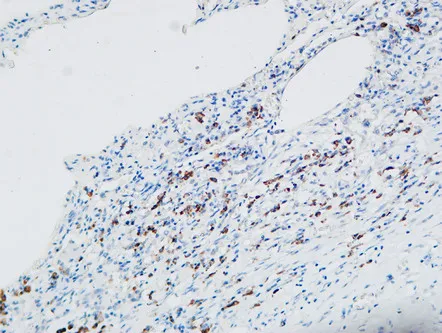

MPO Rabbit Polyclonal Antibody

Cat: APRab14056

Size1:50μl Price1:$118

Size2:100μl Price2:$220

Size3:500μl Price3:$980

Size2:100μl Price2:$220

Size3:500μl Price3:$980